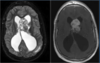

Q

A

Esclerose mesial temporal

Observe a perda de volume, que indica atrofia e causa aumento secundário do corno temporal do ventrículo lateral.

O sinal alto no hipocampo reflete a gliose.

Atrofia hipocampal e hipersinal T2. Cerca de 10% dos casos são bilaterais (dificulta o diagnóstico). A etiologia é desconhecida, mas há uma relação entre STM e convulsões febris prolongadas no início da vida A esclerose mesial temporal pode ocorrer em associação com outras patologias, principalmente displasia cortical focal (dual pathology).